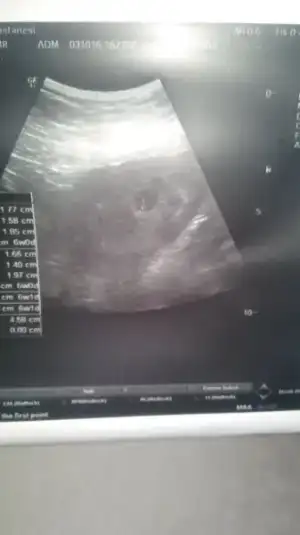

Keseye gore erkek bebisin bence..Havalianne__ Benim ultrason resmime de cinsiyet yorumu yapar misiniz? Vajinal ultrason ve 8 haftalik.Eki Görüntüle 1892583

Havalianne__ Benim ultrason resmime de cinsiyet yorumu yapar misiniz? Vajinal ultrason ve 8 haftalik.Eki Görüntüle 1892583